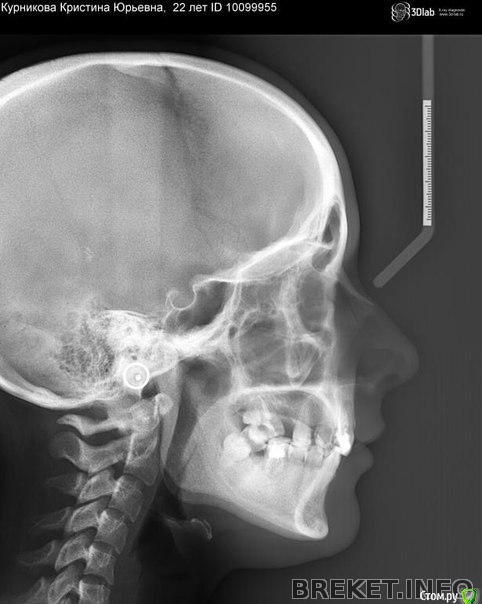

лика54 Опубликовано 8 марта, 2017 Поделиться Опубликовано 8 марта, 2017 Добрый вечер. У меня неправильный прикус 2 класс 2 подкласс (недоразвитие нижней челюсти) . Ношу брекеты 7 месяцев .в будущем времени Планируется ортогнатическая операция , но к сожалению сагитальной щели как таковой пока нет. Ортодонт предлагает установить мини импланты, чтобы верхние резцы быстрее двигались вперед. Подскажите пожалуйста, каким еще способом\способами можно создать эту щель, чтобы ускорить процесс ? Или остановится на орт. винтах? Спасибо Ссылка на комментарий

лика54 Опубликовано 8 марта, 2017 Автор Поделиться Опубликовано 8 марта, 2017 куда планируется установить миниимпланты? Фото зубов покажите пож-та.Насколько я поняла - планируется изменить наклон верхних зубов и сместить центр нижнихНад верхними резцами - 2 штуки.. Скажите пожалуйста. а другие способы возможны? Хочется как можно быстрее чтобы щель появилась и сделать операцию.. Ссылка на комментарий

Brigita Опубликовано 8 марта, 2017 Поделиться Опубликовано 8 марта, 2017 Над верхними резцами - 2 штуки.. Скажите пожалуйста. а другие способы возможны? Хочется как можно быстрее чтобы щель появилась и сделать операцию..Обычно щель быстро появляется.Другие варианты есть.Миниимпланты быстрее, конечно справляются. Ну и плюс если у доктора в плане интрузия зубов при лечении глубокого прикуса. Это возможно старые фото. Скажите пож-та на нижней челюсти сейчас установлены брекеты? Ссылка на комментарий